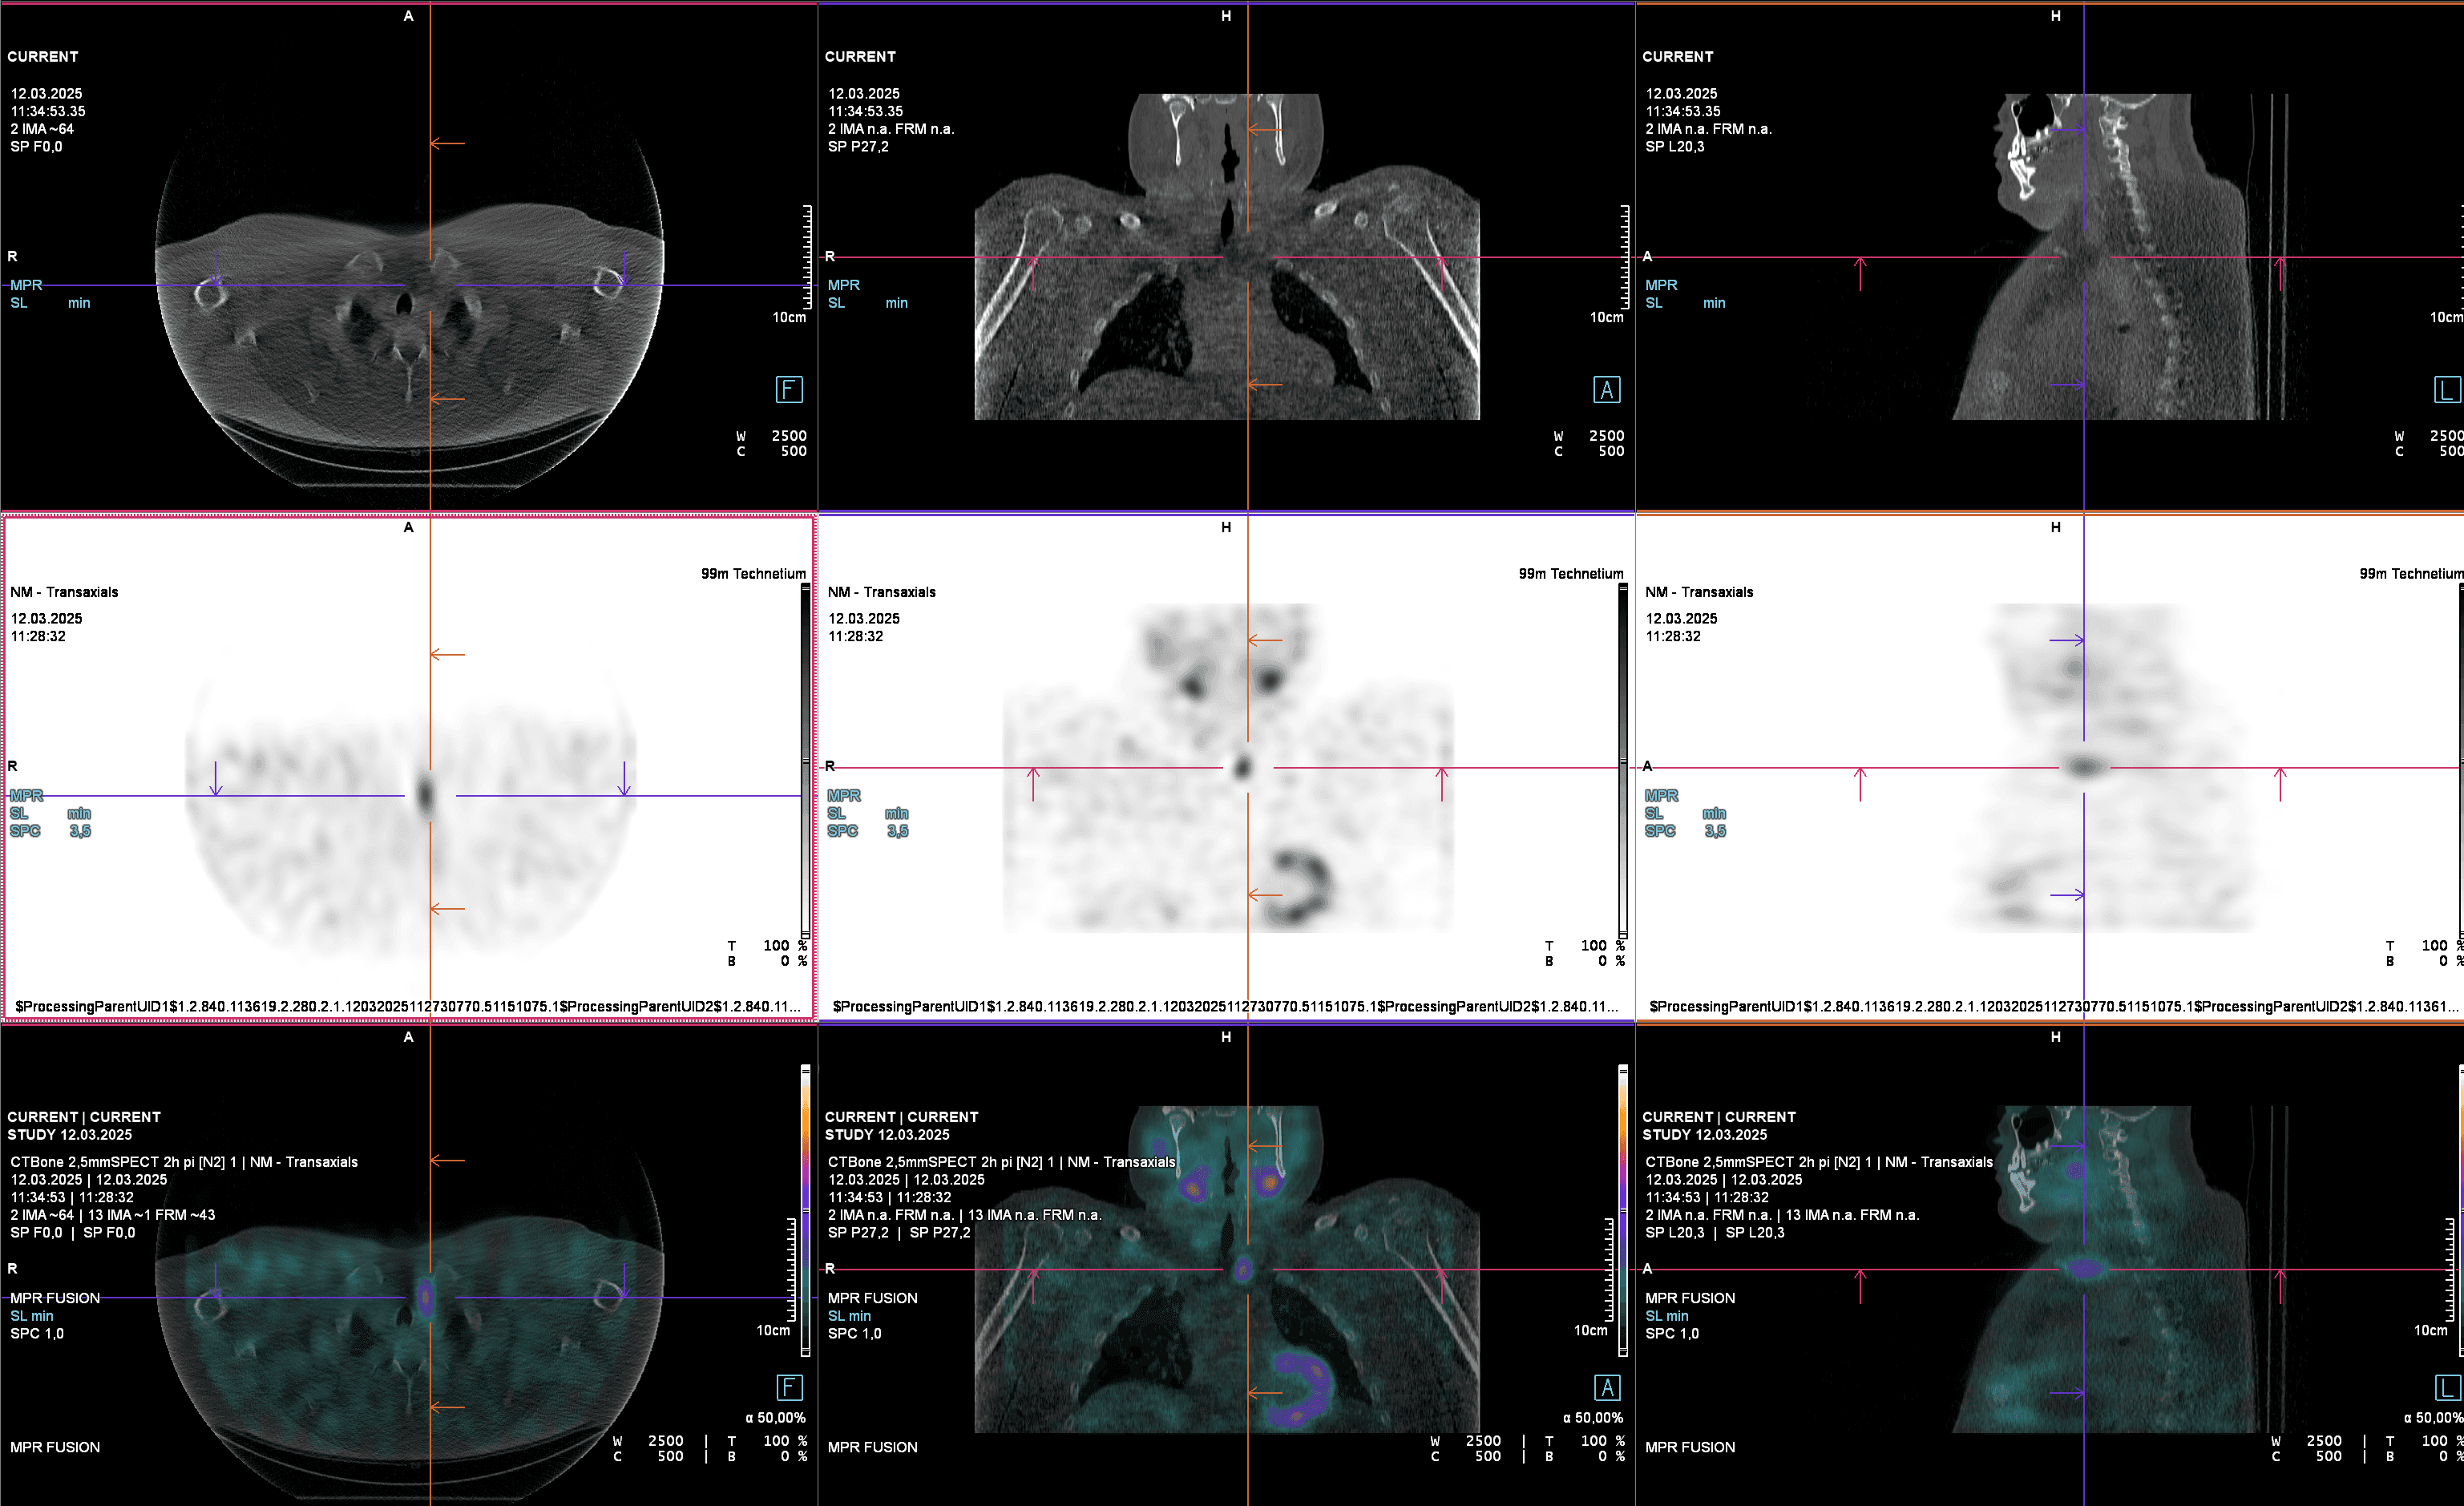

Bone Scintigraphy

Bone Scintigraphy – Whole-Body Imaging for Bone Metastases, Fractures, and Prosthesis Loosening Bone scintigraphy (also called skeletal scintigraphy) is a nuclear medicine imaging technique that visualizes the metabolic activity of the entire skeleton.